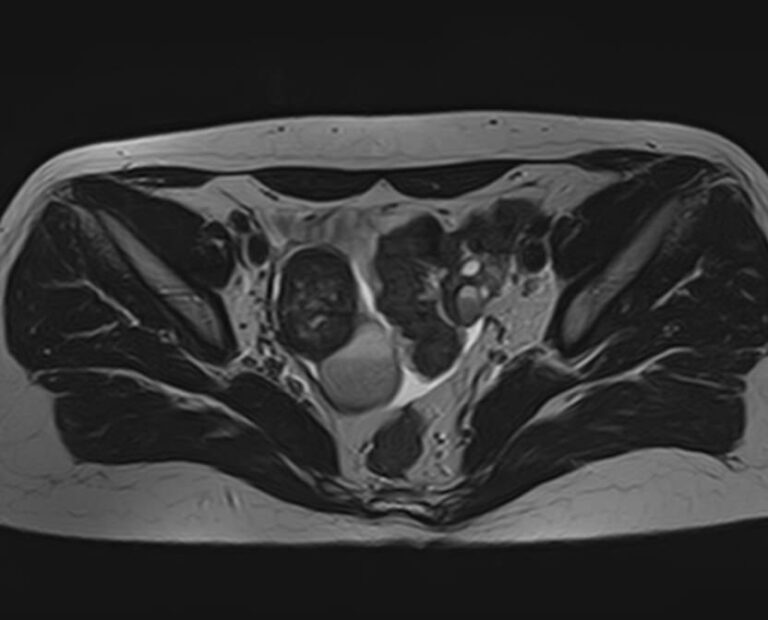

В клинике «Доступная медицина» магнитно-резонансная томография выполняется на высокопольном 32-канальном томографе последнего поколения TOSHIBA VANTAGE TITAN 1,5 Тесла, который обладает высокой разрешающей способностью и обеспечивает непревзойденное качество изображений. Аппарат производит сканирование в трех взаимоперпендикулярных плоскостях и послойными срезами с шагом от 1 мм, что позволяет визуализировать структуру органов и тканей малого таза в мельчайших подробностях. Точная и достоверная информация позволяет выявлять различные заболевания на начальной стадии, от чего напрямую зависит успех лечения.

С помощью данного исследования можно получить детальное послойное изображение матки, яичников, мочевого пузыря и мочеотводящих путей, а также жировой клетчатки, окружающей органы, и лимфатических узлов.

МРТ органов малого таза у женщин может выполняться и с применением контрастного вещества:

• С целью обнаружения или дифференциальной диагностики доброкачественных и злокачественных новообразований;

• Для обнаружения некоторых видов воспаления в мочеполовой сфере;

• Для выявления метастатического поражения органов и тканей малого таза.